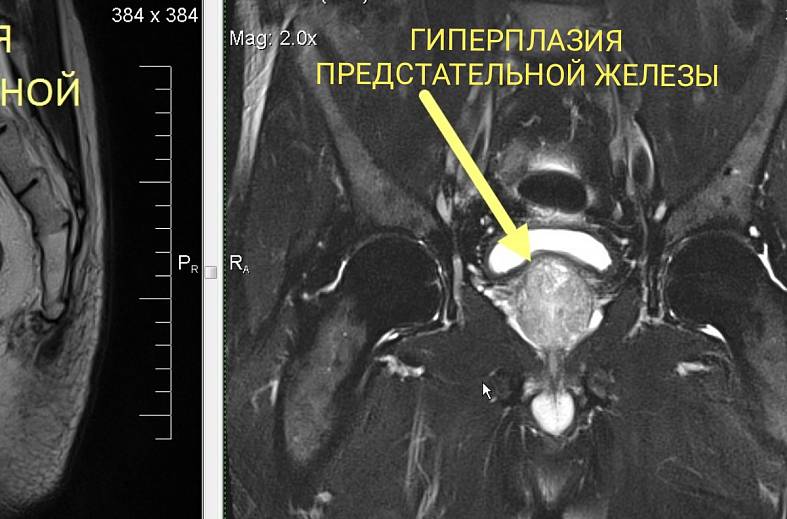

Диагностика заболеваний печени, почек, селезенки и кишечника становится более полной и точной благодаря широкому охвату исследованием․